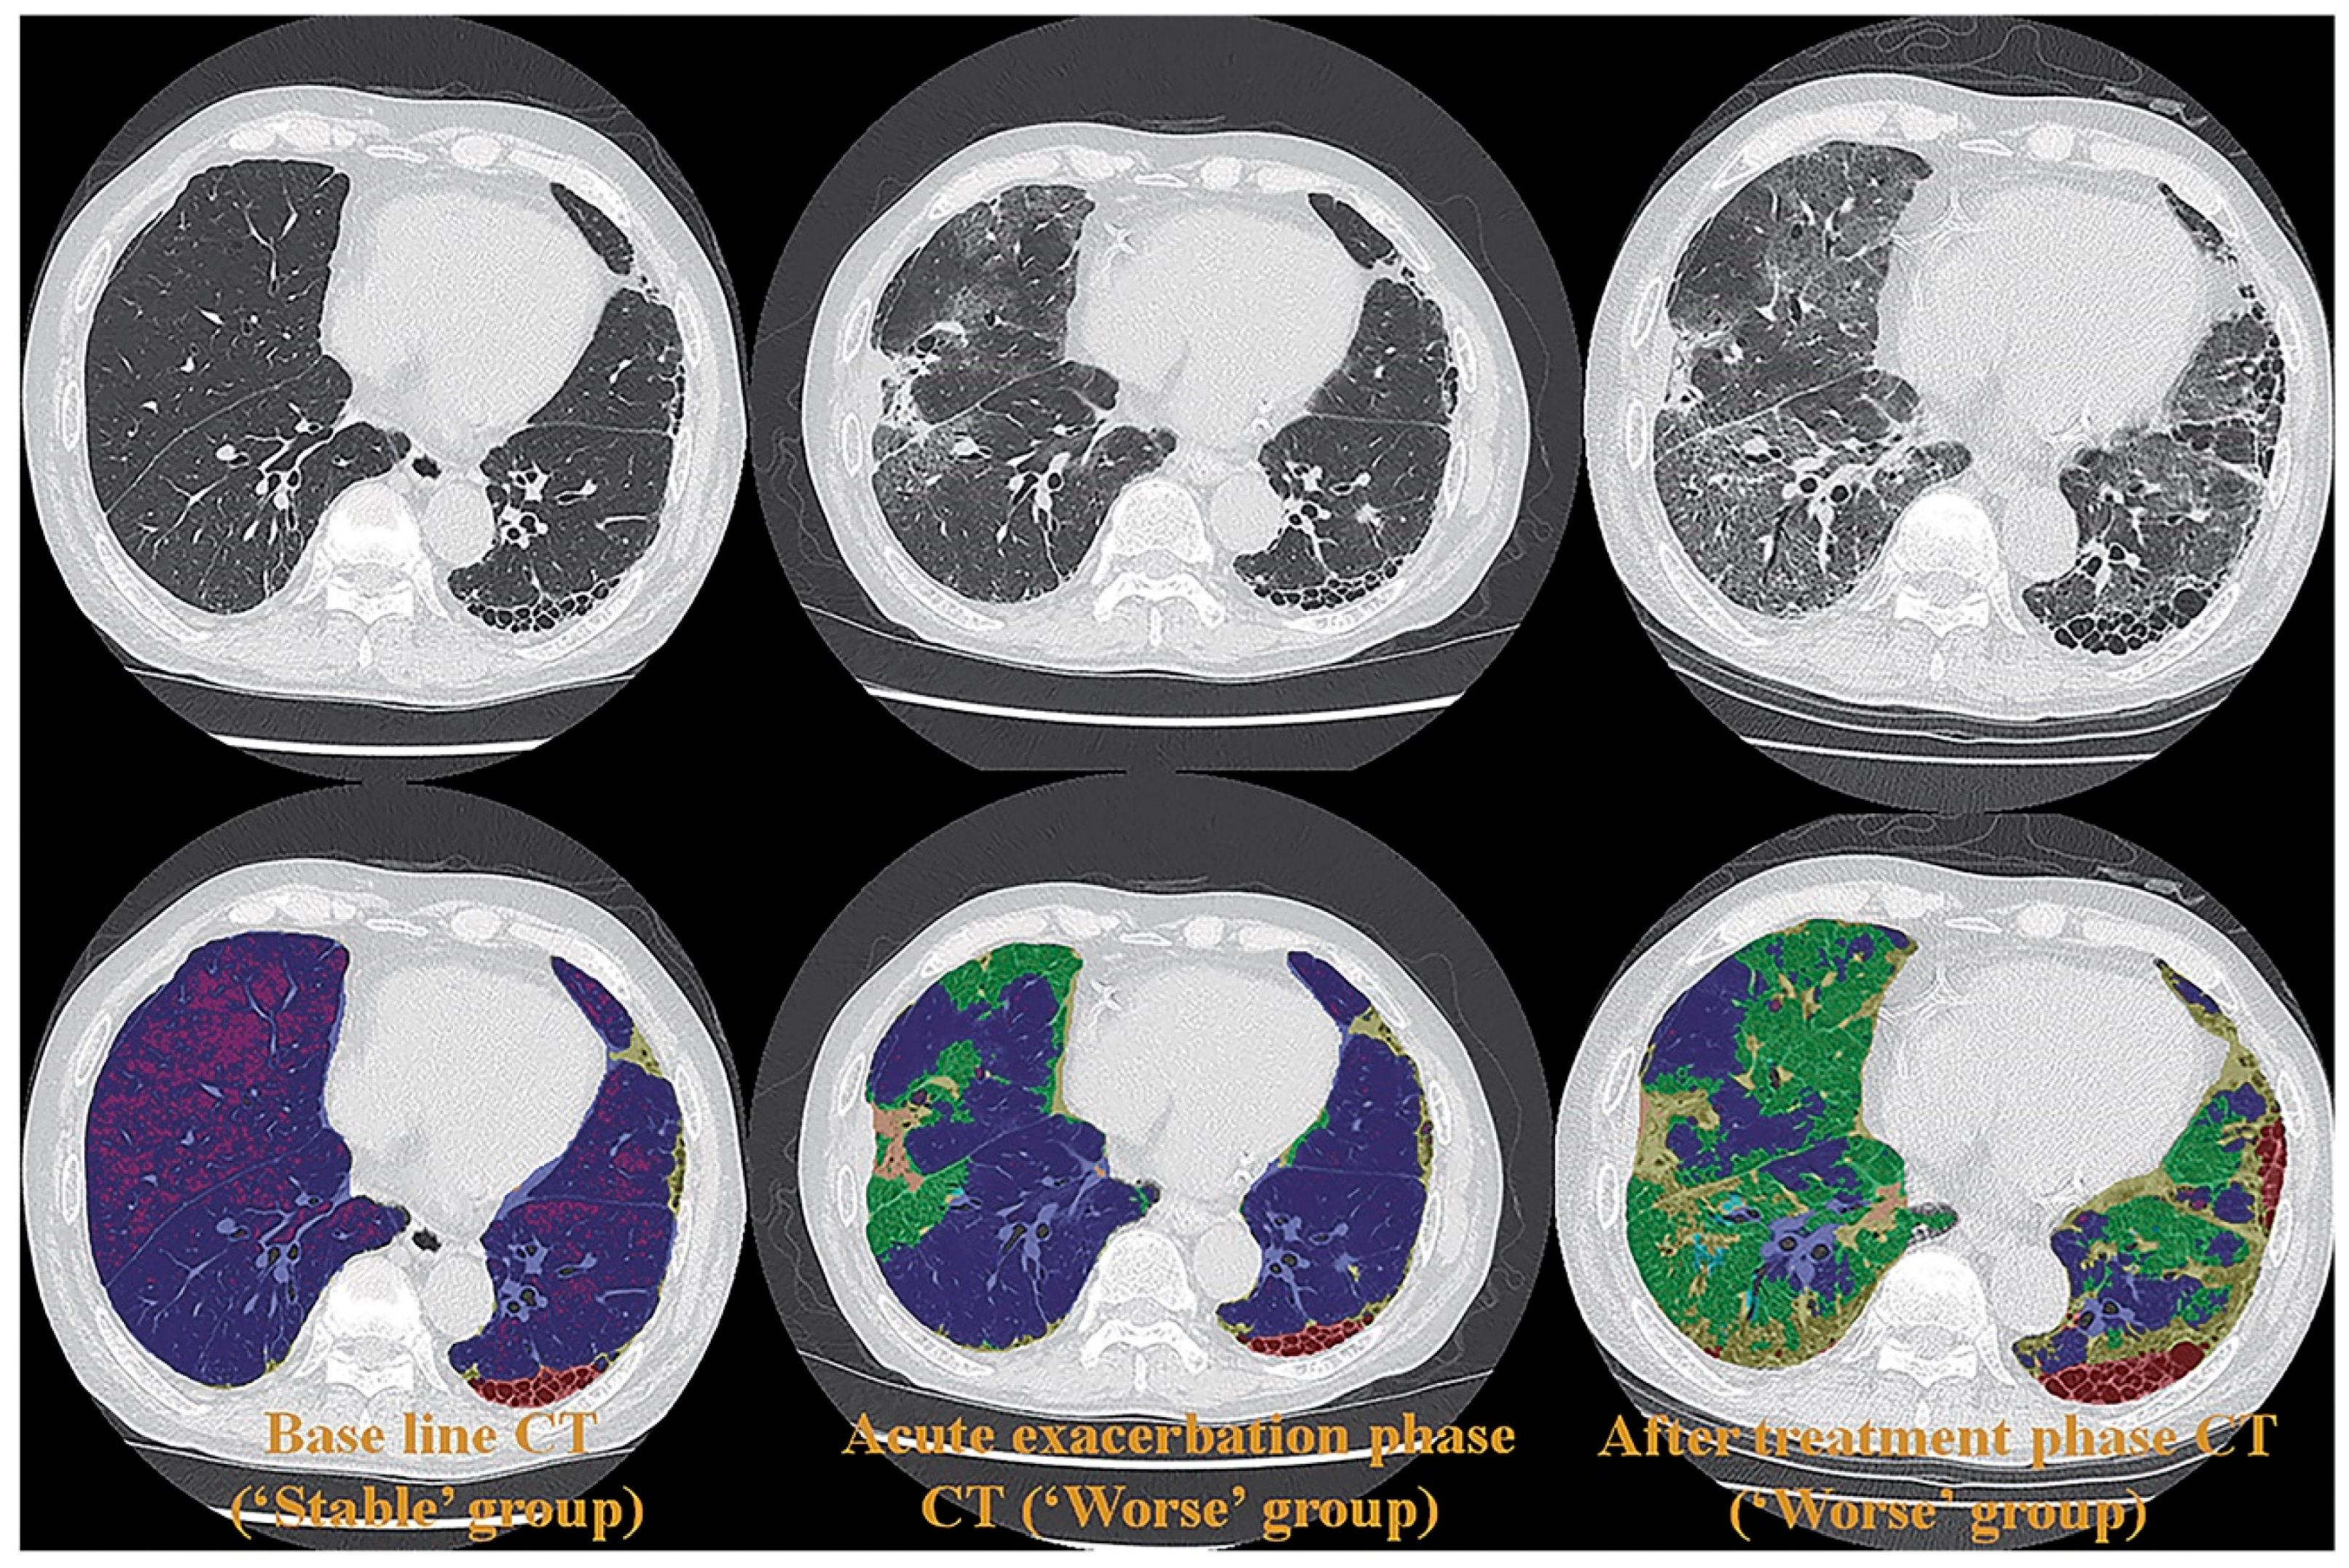

Few studies have been published on radiation dose reduction for the use of ADCT for the quantitative assessment of morphological evaluation of ILD. However, the utility of commercial or proprietary artificial intelligences (AIs) using machine-learning methods by Canon Medical Systems has been evaluated for the management of various lung diseases, such as ILD, or the evaluation of therapeutic treatments for coronavirus disease 2019 (COVID-19) pneumonia, which is caused by severe acute respiratory syndrome coronavirus 2 (SARS-CoV-2) [61,62,63] (Figure 2).

Figure 2.

A 65-year-old female patient with progressive scleroderma (top row, L to R: thin-section CT scans at baseline, acute exacerbation phase, and after-treatment phase; bottom row, L to R: CT texture analysis by means of machine-learning-based software at baseline and the same two phases as for the top row) (permission from reference [63]). On machine-learning software, normal lung, consolidation, emphysema, GGO, honeycombing and reticulation are expressed as blue, beige, purple, green, red and green. A comparison of CT scans obtained at baseline (i.e., “Stable” group) and at the acute exacerbation phase (i.e., “Worse” group) shows an increase in the GGO and the consolidation area and a decrease in the normal lung area. Δ% normal lung, Δ% GGO, and Δ% consolidation were −16.9%, 13.2%, and 2.5%, respectively, while Δ disease severity score was 6. A comparison of CT scans obtained at the acute exacerbation phase (i.e., “Worse” group) and the after-treatment phase (i.e., “Worse” group) shows an increase in the GGO, reticulation, and honeycomb area and a decrease in the normal lung area. Δ% normal lung, Δ% GGO, Δ% reticulation, and Δ% honeycomb were −19.5%, 14.9%, 4.2%, and 0.2%, while Δ disease severity score was 15. CT, computed tomography; GGO, ground-glass opacity.

These studies were the first to demonstrate the potential of AI in the evaluation of disease severity and therapeutic effect or of functional changes due to treatment with an accuracy similar to that attained by board-certified radiologists [61,62,63]. Although further investigations are warranted, the evaluation of ADCT by AI has opened new areas for the application of pulmonary functional ADCT in not only ILD but also other diseases.